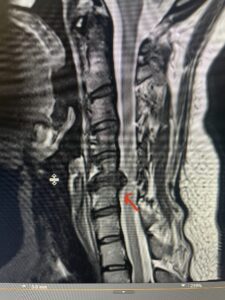

This 36-year-old female who had a long history of neck pain had a history on MRI of a C5-6 bulge. She recently after diving into a pool (not hitting her head on bottom) developed progressive problems with her arms. She had developed spontaneous shocks going down her arms and in the back of her neck. Spontaneous shocks going down the neck and spine is called a Lhermitte’s phenomenon and can occur with spinal cord compression and also with multiple sclerosis. On examination, the patient had long tract weakness of her arms, right greater than left. Her finger extensor weakness was profound on the right. MRI (Fig. 4) of the cervical spine revealed a massive C5-6-disc herniation causing significant cord compression right greater than left with subtle cord signal change. Because of the severe myelopathy, the patient was indicated for surgery. A C5-6 anterior cervical discectomy and fusion was performed (Fig. 5). The patient had a dramatic improvement of her strength in the recovery room.

Fig 4. Axial T2-weighted MRIs demonstrating large C5-6 herniated disc with spinal cord compression (red arrow)

Fig 4A. Axial T2 weighted MRIs demonstrating large C5-6 herniated disc with spinal cord compression (red-arrow)